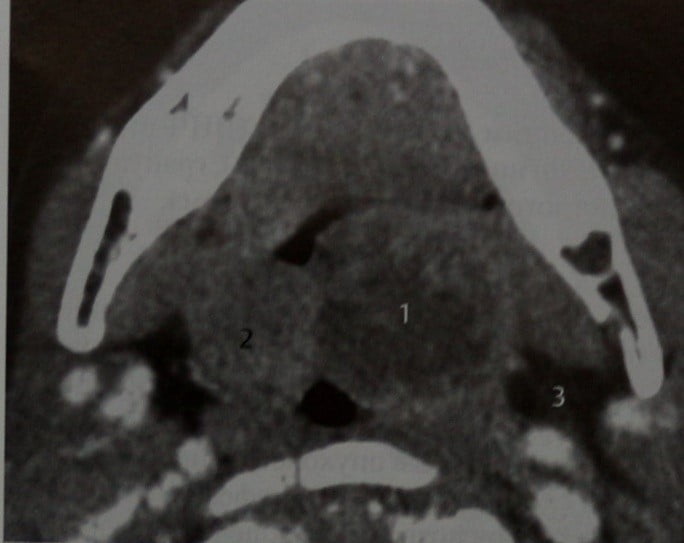

КТ-исследование абсцесса малого таза: Визуализация и диагностика

Раздел: Фотоальбом решений